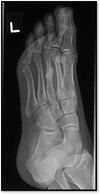

What type of fracture is shown on the Medial border of the 3rd metatarsal?

Stress fracture | (see the pariosteal reaction)

98

What pathology is present?

March fracture